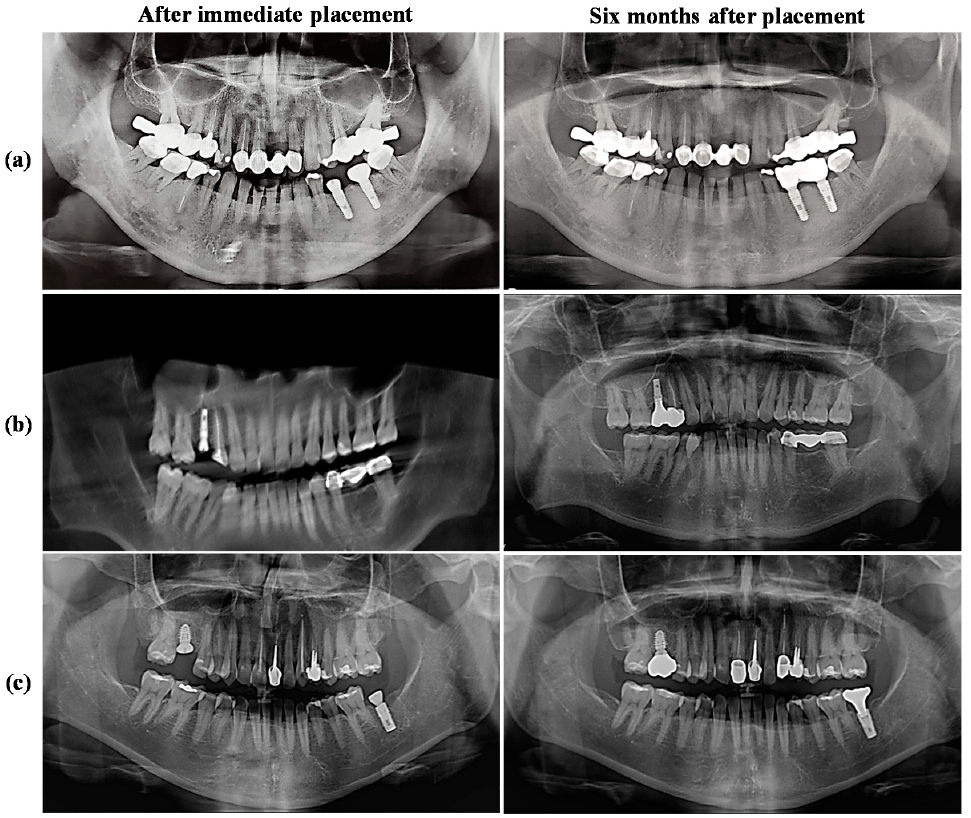

3.5. Radiograph Evaluations of the IDCT-Ti/GRGD-1 Implant